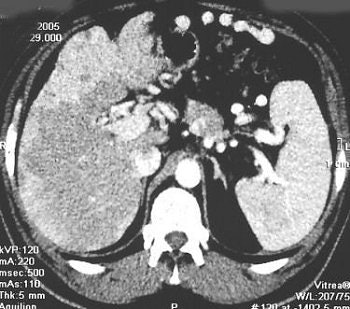

![]() |

| Same case as above. 111In-pentetreotide SRS provided a doubtful result with negative images 4 hours after injection of 111In-pentetreotide (left) and a doubtful abdominal focus 24 hours after injection (right). Primary small bowel carcinoid was subsequently successfully resected. Copyright © 2006 by the Society of Nuclear Medicine. |